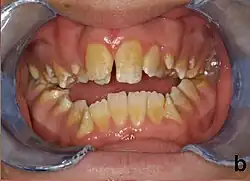

Signs of plane-form enamel hypoplasia can be observed through pitting, depressions, and grooves seen on the surface of the teeth. This disease can solely affects a person's teeth, causing the enamel on one's teeth to erode. Common signs include white spotting and yellow or orange discoloration on the tooth surface. Patients with this condition often experience weakened and sensitive teeth. Progressive eroding of the enamel causes the teeth to become more sensitive, leading to discomfort when eating or drinking.[4]